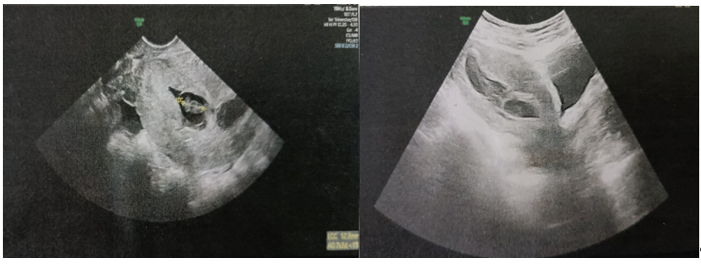

• Pelvic ultrasound (09/25/2024) (figure 2): globular uterus with hypotonic intra cavitary gestational sac with isthmic projection and embryo without AC, LCC of 11mm corresponding to 7SA.

Figure 2: Gestational Sac with Isthmic Projection Containing an Embryo with no Cardiac Activity